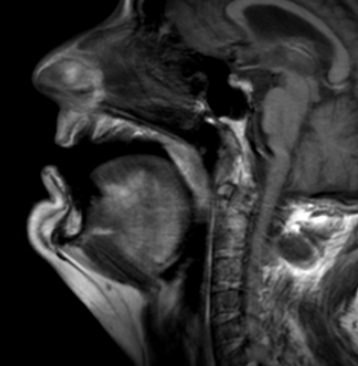

Fig 1. MRI scan depicting the upper airway of a patient diagnosed with severe Obstructive Sleep Apnea (OSA).

The initial and critical step for a Computational Fluid Dynamics (CFD) project on sleep apnea is the Magnetic Resonance Imaging (MRI) image acquisition. This involves capturing a series of high-resolution, cross-sectional images of a patient’s upper airway (including the nasal passages, pharynx, soft palate, and tongue). MRI is particularly advantageous over other imaging modalities like CT because it offers superior soft-tissue contrast, which is essential for clearly delineating the airway’s collapsible structures -the primary contributors to obstructive sleep apnea (OSA). Depending on the project goal, a static MRI (e.g., at end-exhalation) may be used to capture the detailed resting anatomy, or a dynamic “cine” MRI sequence may be used to capture the airway’s motion throughout a breathing cycle. These DICOM-formatted image slices serve as the foundational dataset, providing the precise, patient-specific anatomical boundaries required for the subsequent 3D model reconstruction and CFD simulation.